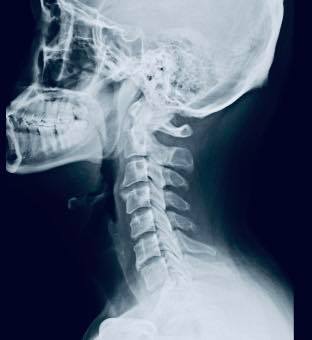

😂😂林先生在十年前出一場嚴重車禍導致胸椎跟頸椎受傷,X光片顯示頸椎前緣骨質增生、第二第三關節突增生、第六第七關節突卡壓 ,胸椎歪斜,最困擾症狀是上背悶痛,這幾年幾乎每周都會安排推拿,可以緩解胸悶的情況,但是一直沒有重大改善,狀況不好的時候也會引發背痛 ,來診前的這幾個月幾乎是每天都會痛,經過友人介紹來接受脊椎整合中醫微創療法

✳️診斷:胸椎小關節面沾黏合併頸椎神經根卡壓